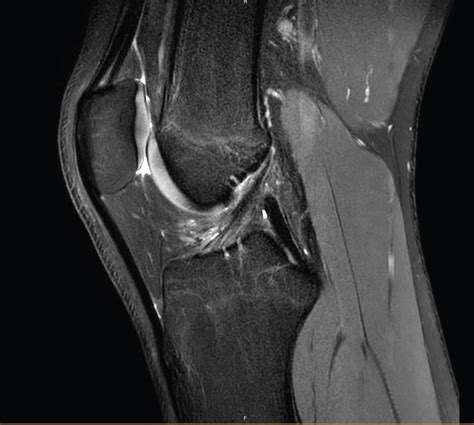

Diagnosing Biceps Femoris Tendinosis

Diagnosing Biceps Femoris Tendinosis involves a combination of physical examination and imaging tests. A healthcare professional will typically:

• Imaging Tests: Order imaging tests such as ultrasound or MRI to visualize the tendon and confirm the diagnosis. These tests can help identify degeneration, thickening, or other abnormalities in the tendon.